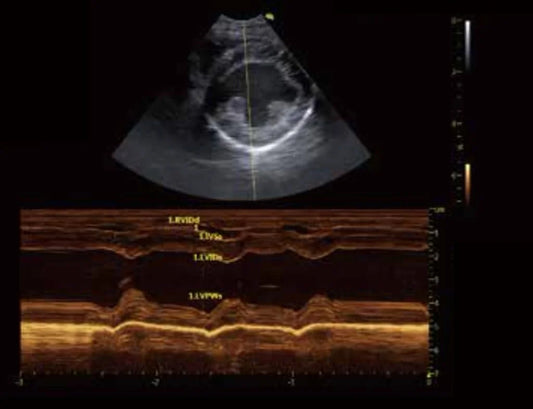

Ecocardiografía en Veterinaria: Monitoreo Preci...

La ecocardiografía es una herramienta esencial en la evaluación del corazón de los animales, permitiendo observar en tiempo real su estructura y funcionamiento sin procedimientos invasivos. La imagen obtenida con...